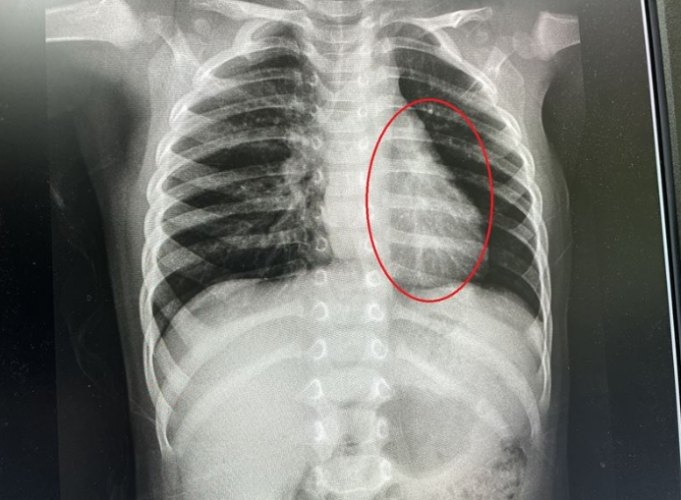

1.3 「非典型肺炎」的典型病原

- 胸部X光:可能顯示局部或廣泛的間質性肺炎變化(如網狀或斑片狀浸潤),有時變化輕微甚至正常。